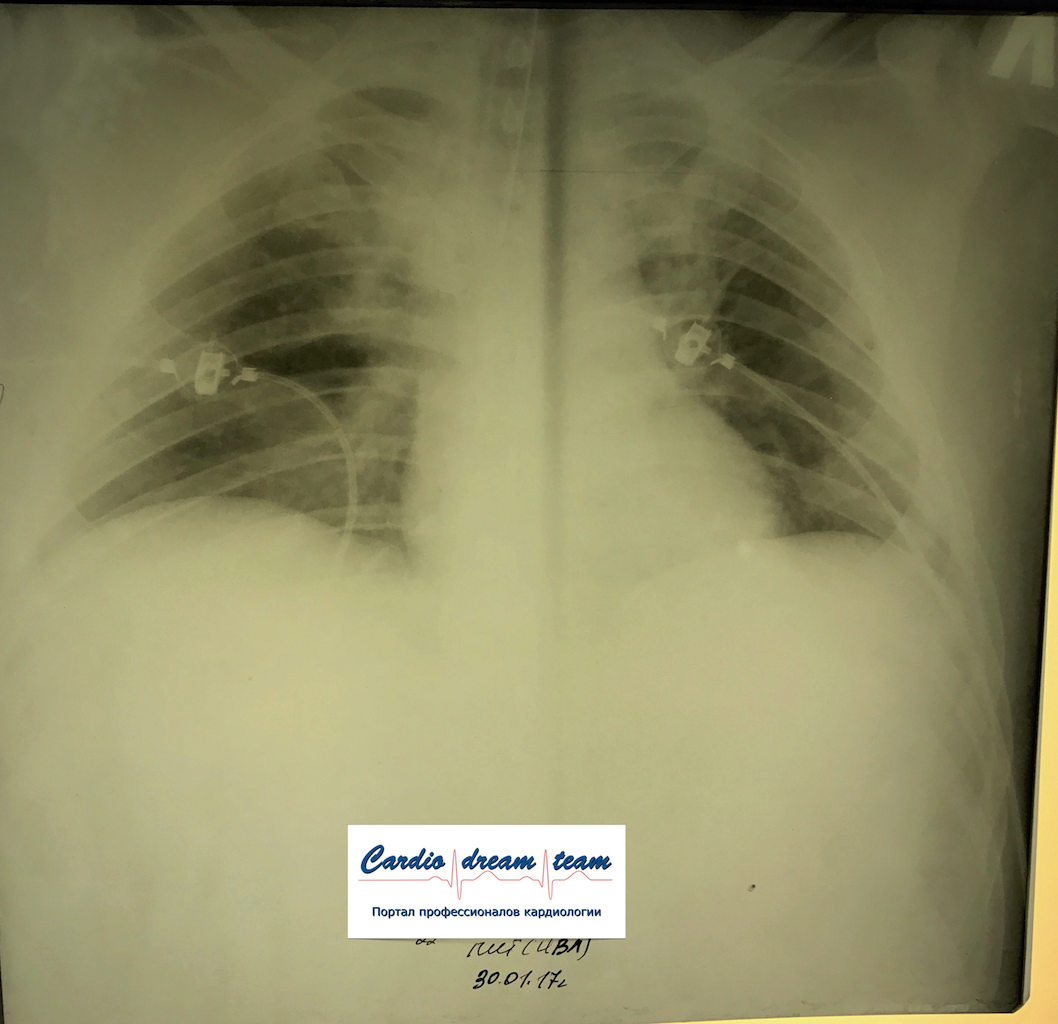

М 35 лет наркоман. Аспирация рвотных масс. До санации и после.

IMG_5519.png

IMG_6456.png